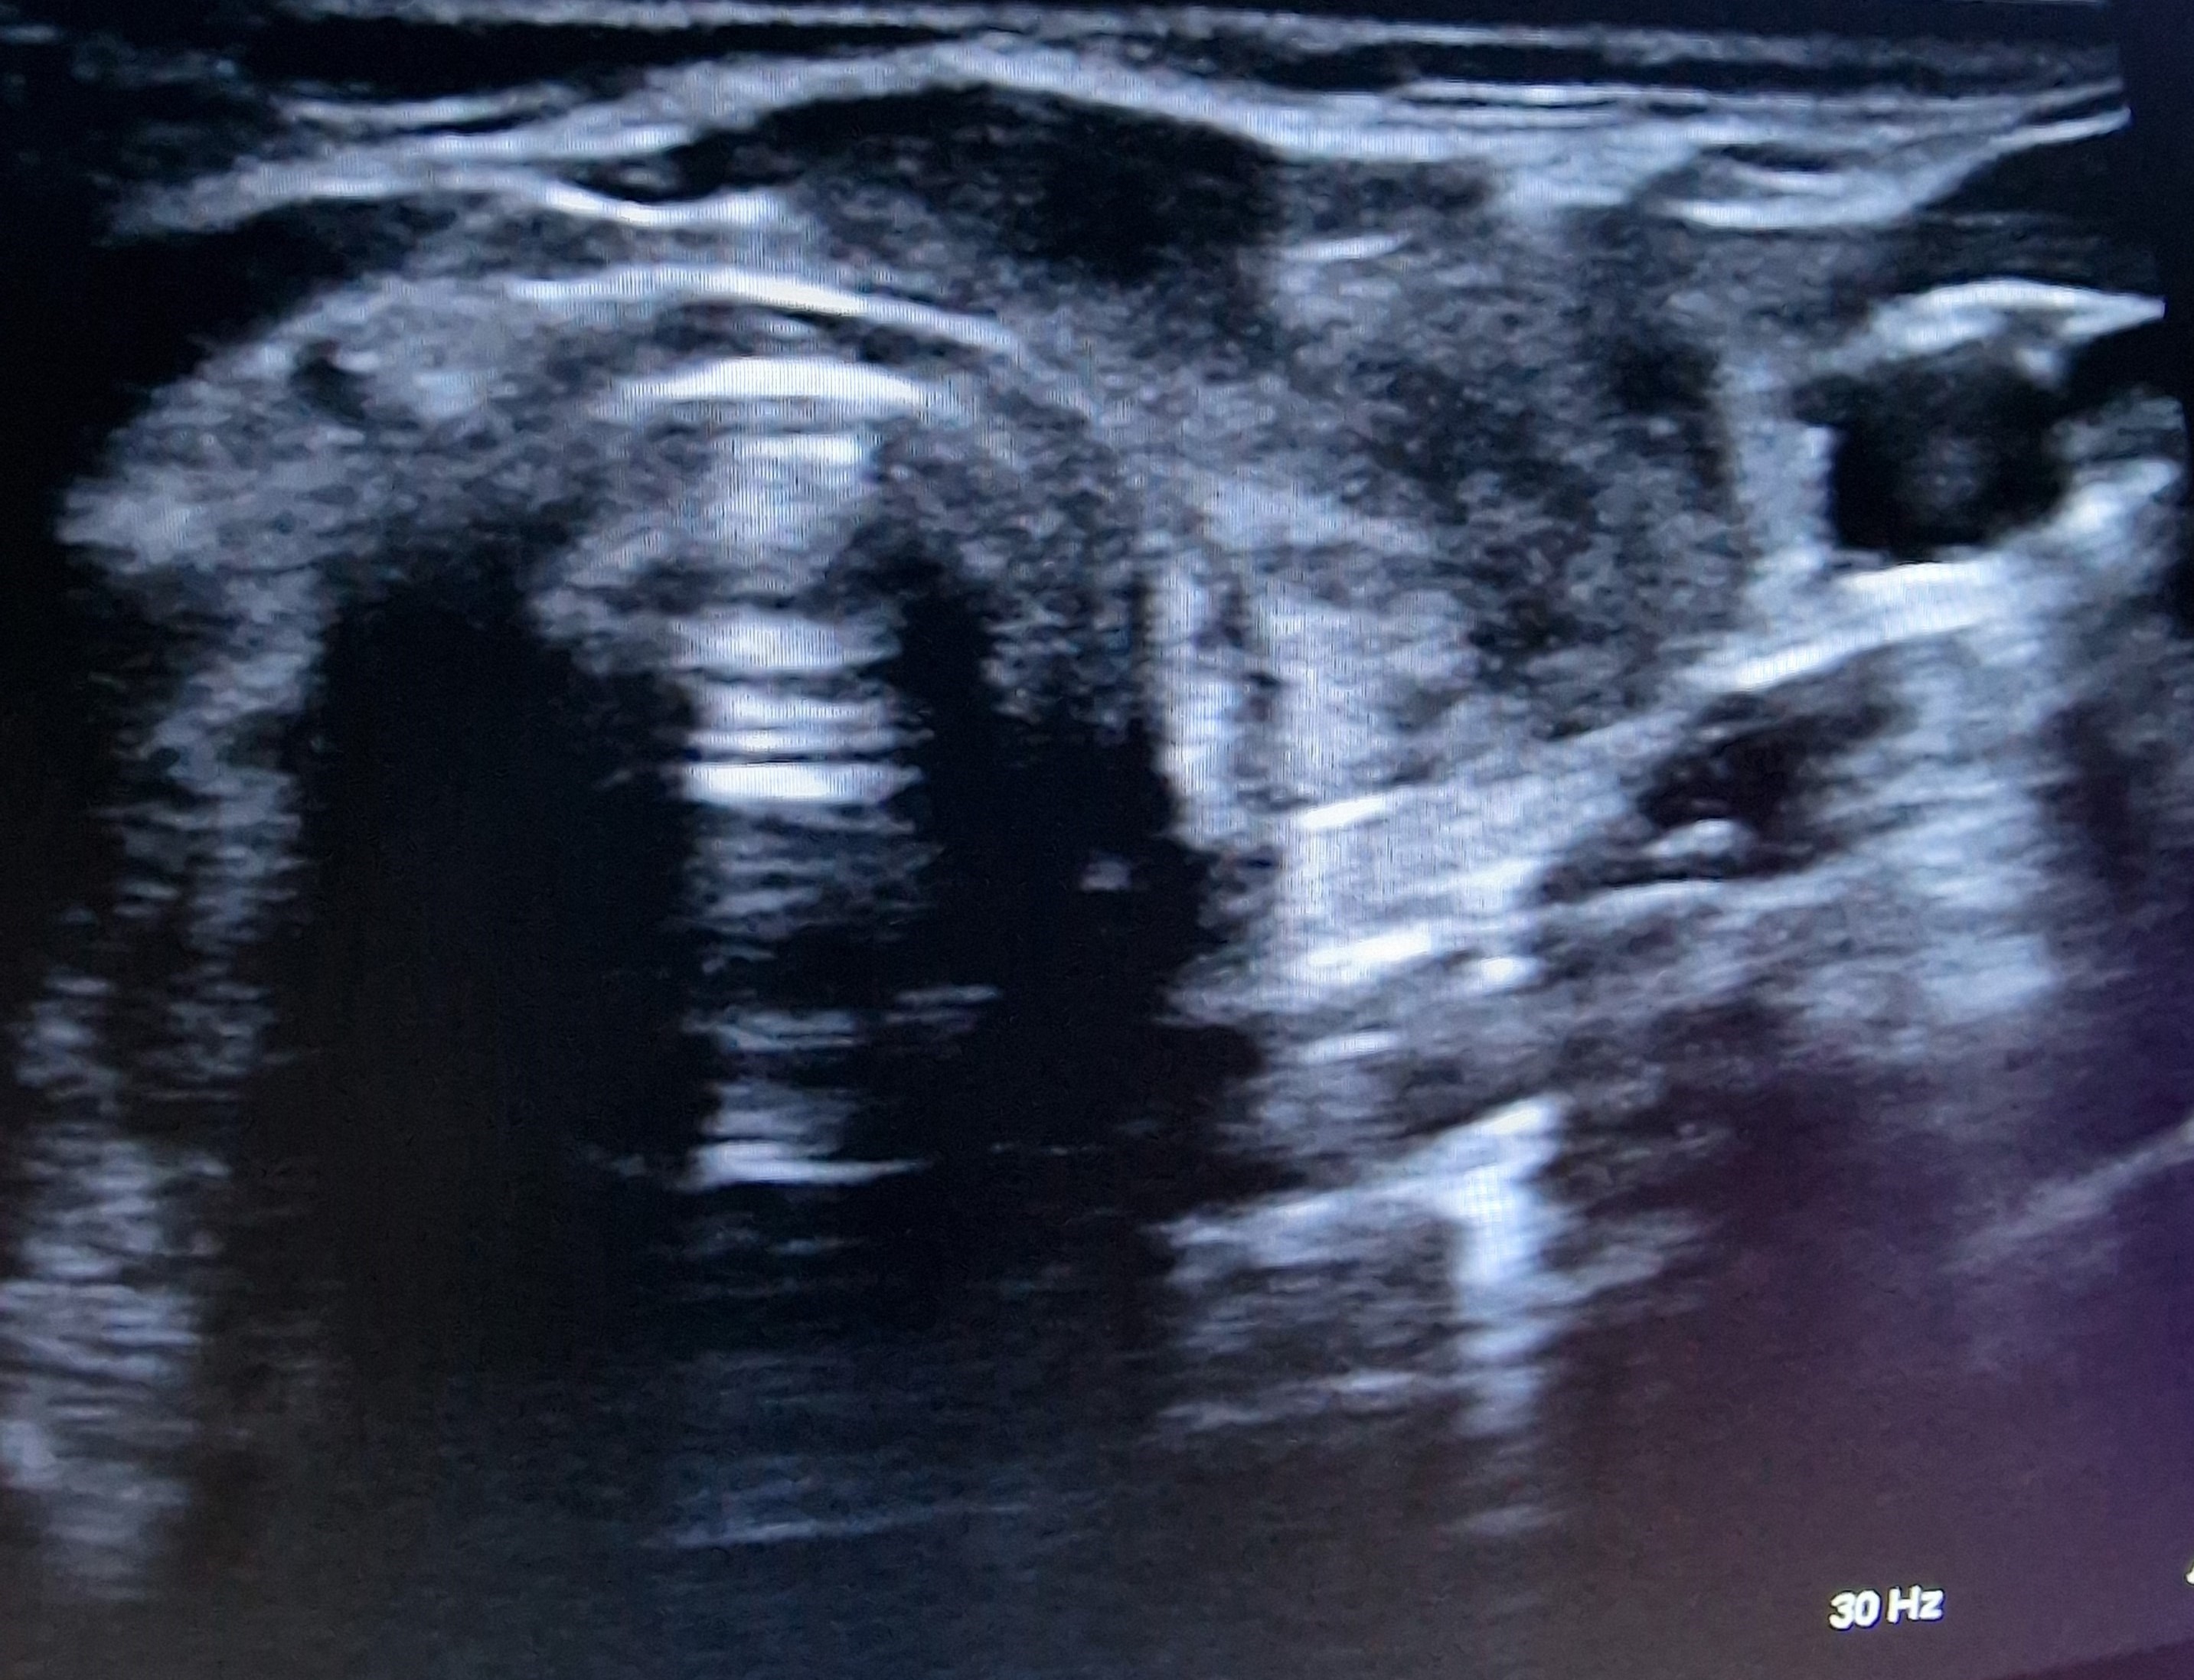

Ecografía cervical: tiroides de ecogenicidad heterogénea con áreas hipoecogénicas y ausencia de vascularización de éstas, Lóbulo Tiroideo Derecho 20 x 14 mm con nódulo < 10 mm no maligno e izquierdo 16 x 12 mm.

Se decide realizar ecografía de cuello ante fiebre sin otro foco, dado dolor cervical anterior, para estudio de posible origen tiroideo.

Ante cuadro de fiebre sin foco es importante un adecuado diagnóstico diferencial e historia clínica. Este tipo de tiroiditis es la causa más frecuente de dolor tiroideo, más frecuente en mujeres; de etiología desconocida, aunque frecuentemente aparece tras infección vírica de vías respiratorias altas. La ecografía es la prueba de imagen de elección para diagnosticarla, remarcando por tanto la utilidad de ella para el diagnóstico de patología sin sintomatología florida.